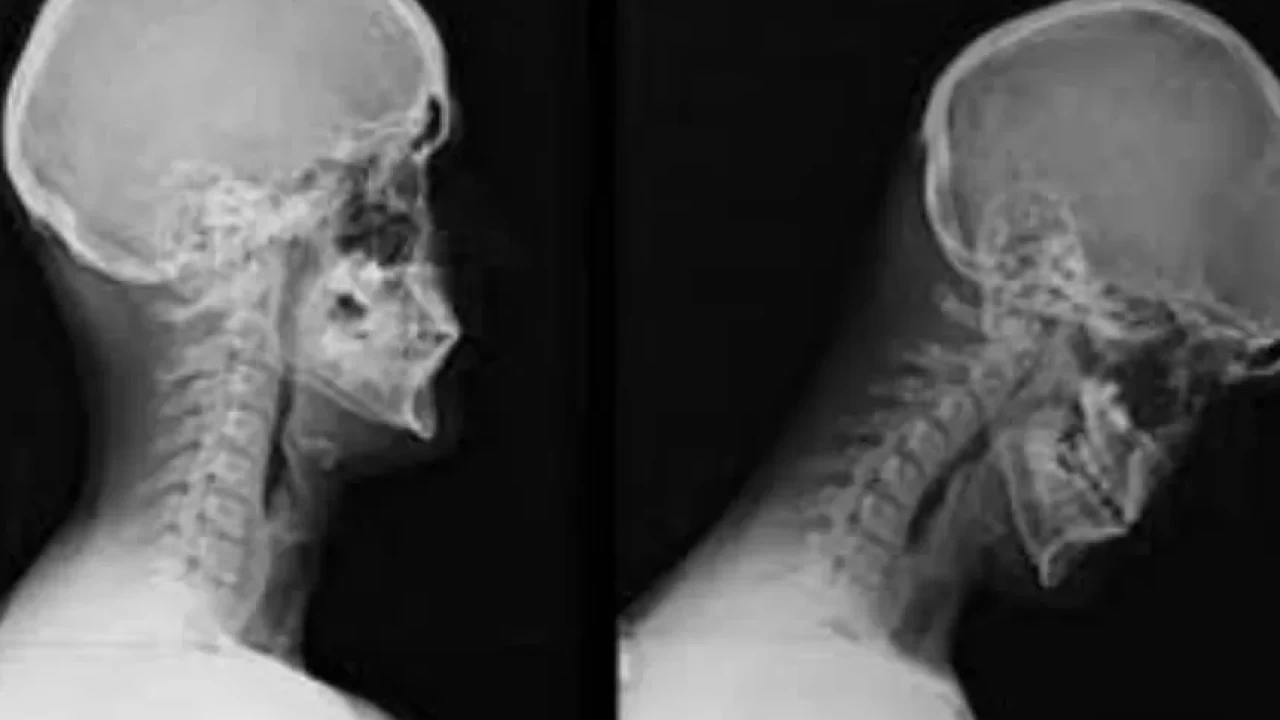

Cep Boyun Sendromu (Text Neck), özellikle akıllı telefonlar, tabletler ve bilgisayarların aşırı kullanımına bağlı olarak gelişen bir postür bozukluğudur. Uzun süre başın öne eğilmesiyle boyun, omuz ve sırt bölgesinde ağrı, kas gerginliği ve postür bozukluklarına neden olan bu sendrom, günümüzde teknoloji bağımlılığının yaygınlaşmasıyla daha fazla kişiyi etkiliyor. Peki, cep boyun sendromunun belirtileri nelerdir ve nasıl önlenebilir? Uzmanlar bu soruları yanıtladı.

Cep boyun sendromunun başlıca belirtileri, boyun, omuz ve sırt bölgesinde ağrı ve sertlik, baş ağrıları, hareket kısıtlılığı, elde uyuşma ve karıncalanma gibi semptomlardır. Bu belirtiler zamanla daha da şiddetlenebilir ve omurga eğrilikleri ile postür bozukluklarına yol açabilir.